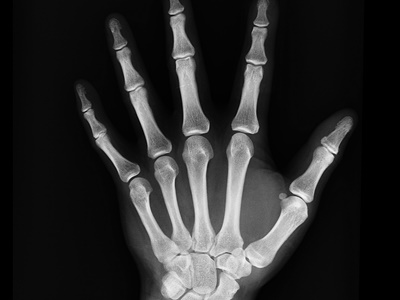

콘드로이친(Chondroitin)은 연골의 주요 구성 성분 중 하나로, 관절을 부드럽게 움직이게 해주는 윤활제 역할을 해요. 자연적으로 우리 몸 안에 존재하지만, 나이가 들수록 그 양이 줄어들면서 관절이 뻣뻣하거나 통증이 생기기 쉬워지죠. 보충제로 복용하면 연골을 보호하고 재생을 돕는 데 효과적이라고 알려져 있어요.